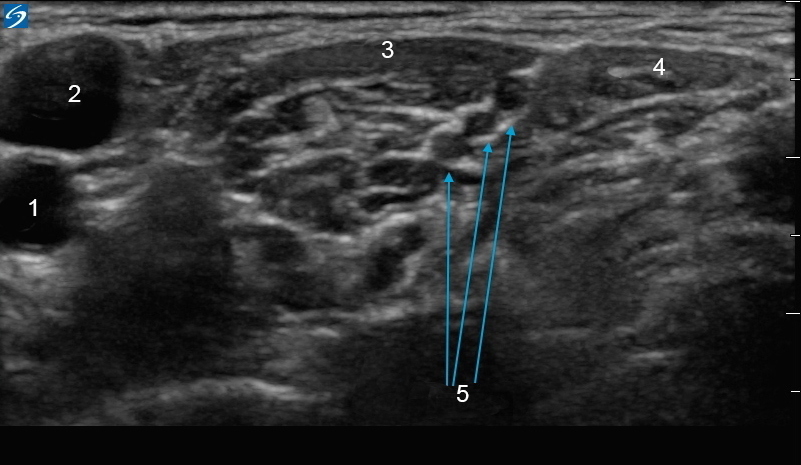

1. A. carotis

2. Vena jugularis

3. M. scalenus anterior

4. Musculus scalenus medius

5. Nerven